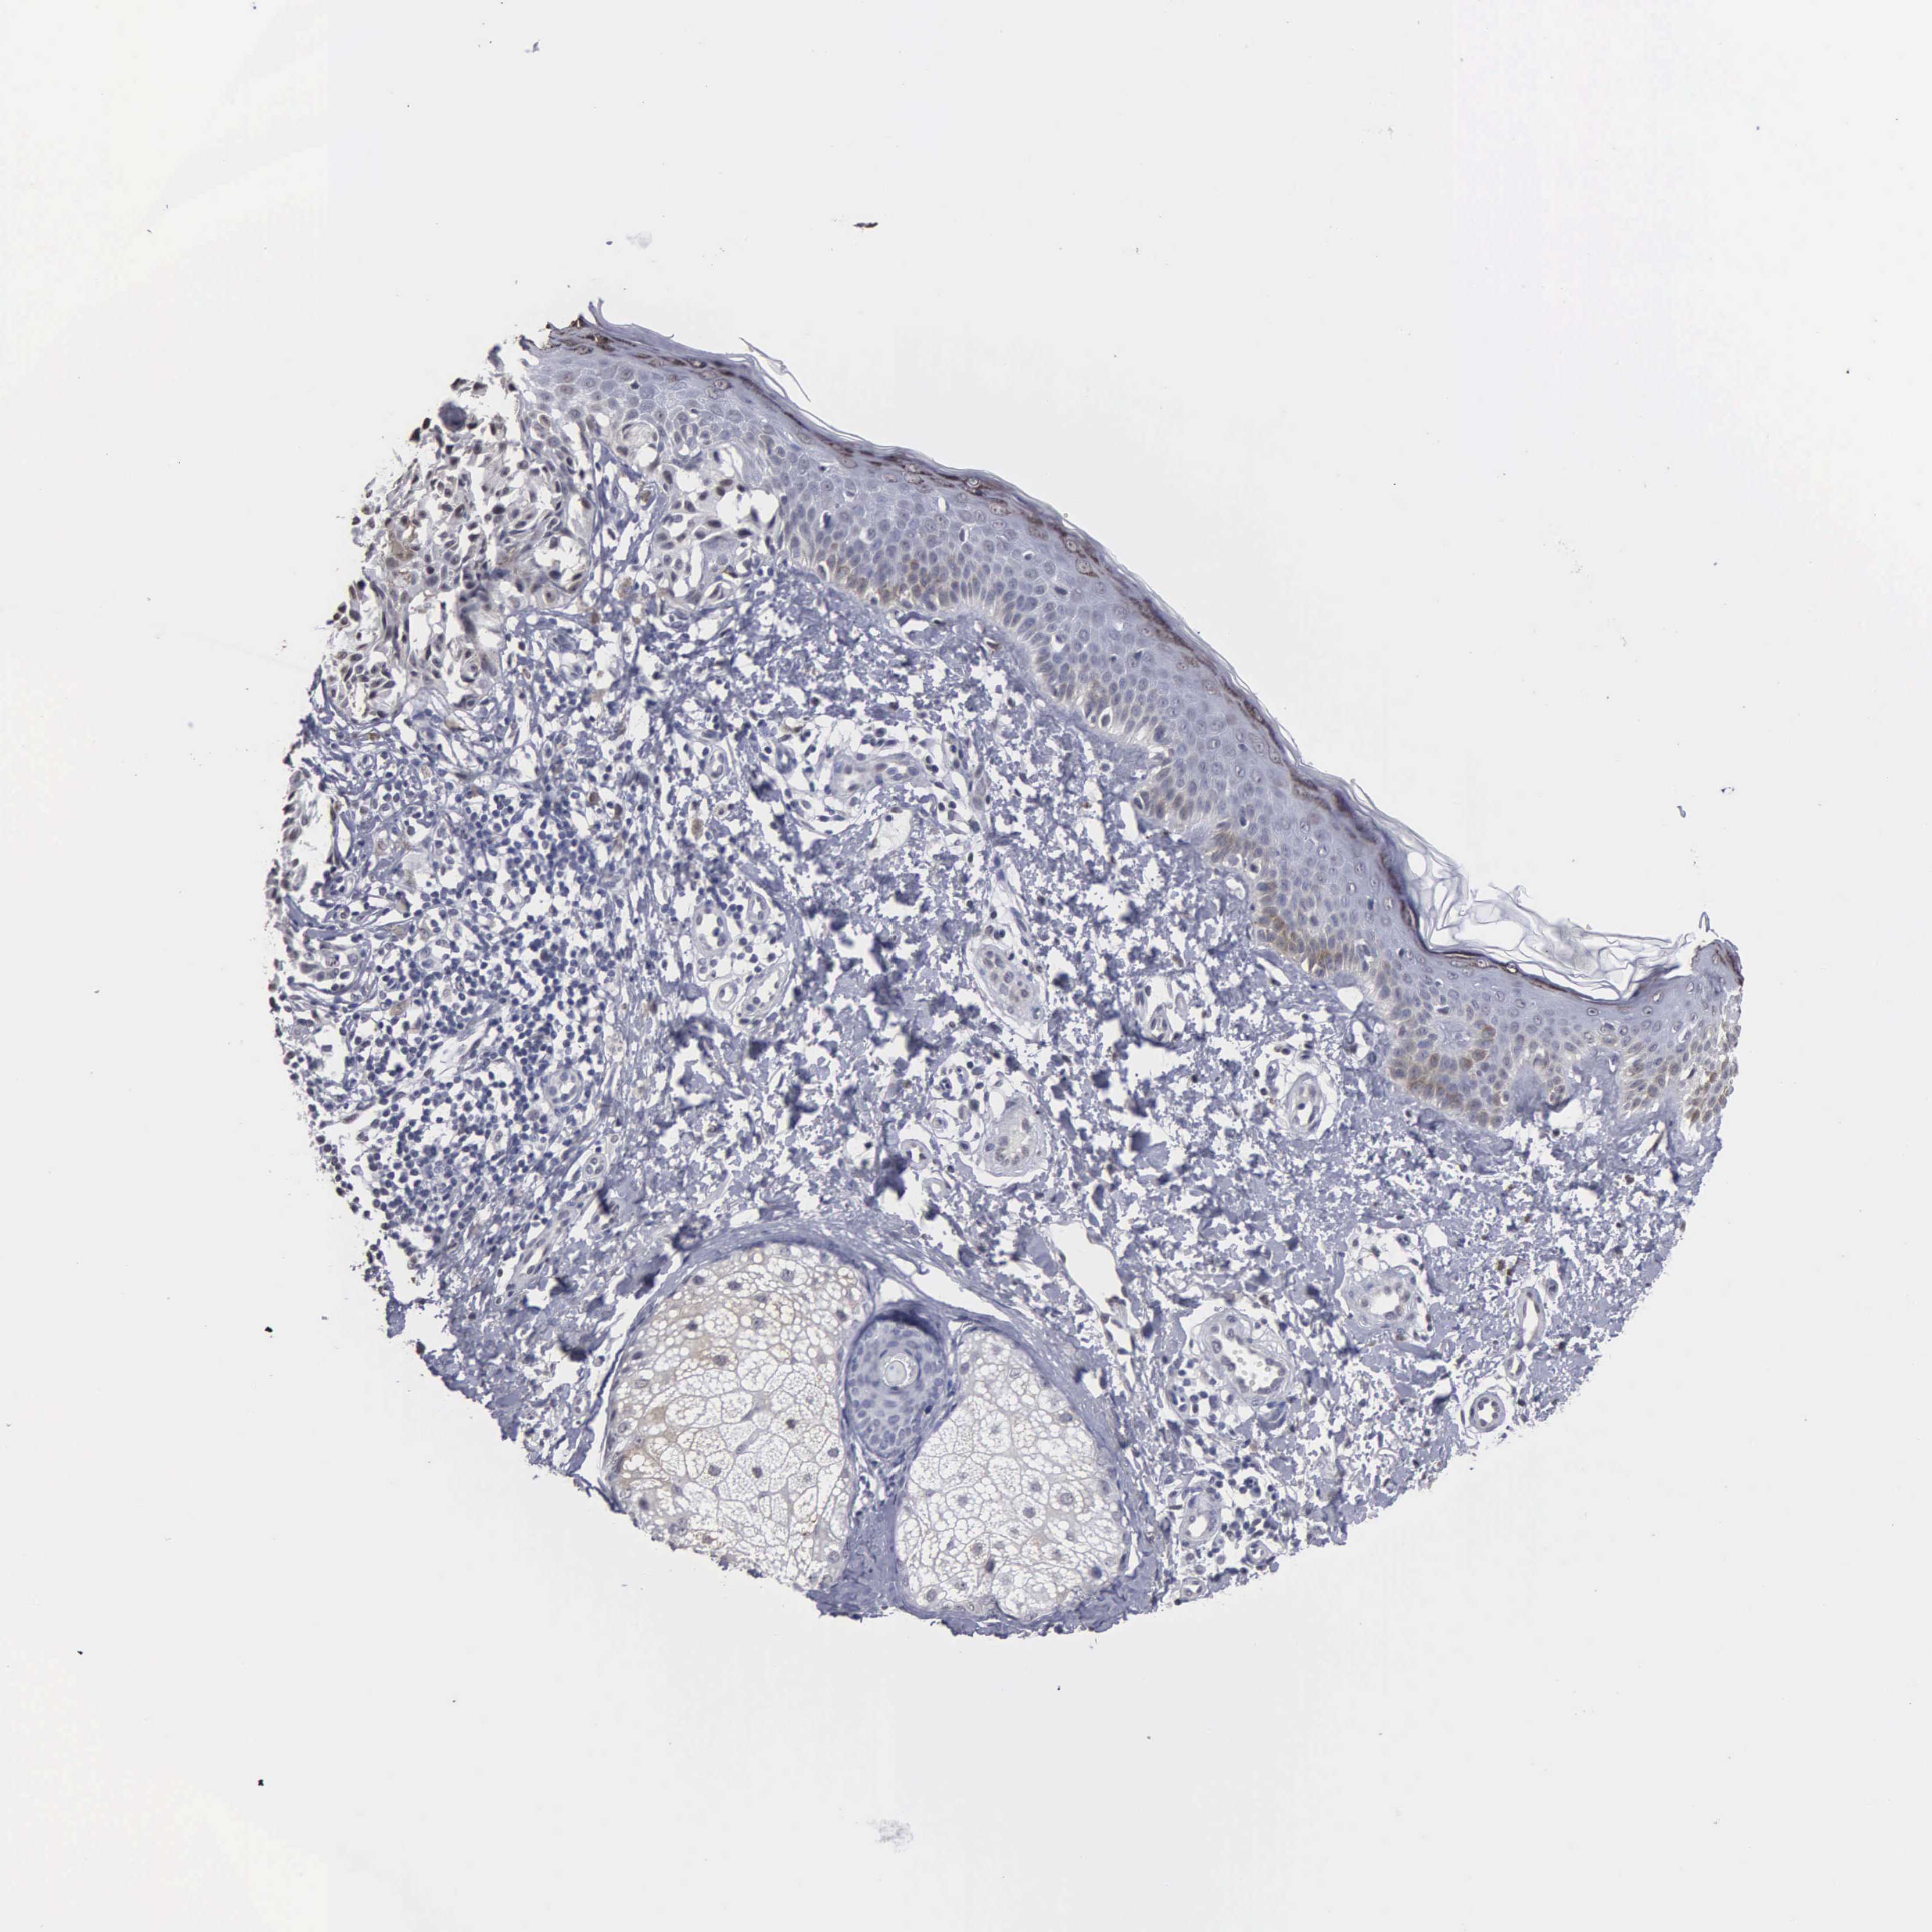

MELANOMA - Protein expressioni

A mouse-over function shows sample information and annotation data. Click on an image to view it in a full screen mode. Samples can be filtered based on level of antibody staining by selecting one or several of the following categories: high, medium, low and not detected. The assay and annotation is described here.

Note that samples used for immunohistochemistry by the Human Protein Atlas do not correspond to samples in the TCGA dataset.

Antibody stainingi

Antibody staining in the annotated cell types in the current human tissue is reported as not detected, low, medium, or high, based on conventional immunohistochemistry profiling in selected tissues. This score is based on the combination of the staining intensity and fraction of stained cells.

Each image is clickable and will lead to virtual microscopy that enables deeper exploration of all samples and also displays staining intensity scores, fraction scores and subcellular localization as well as patient and tissue information for each sample.

Antibody HPA000728

Antibody HPA076321

Malignant melanoma, NOS

Malignant melanoma, Metastatic site